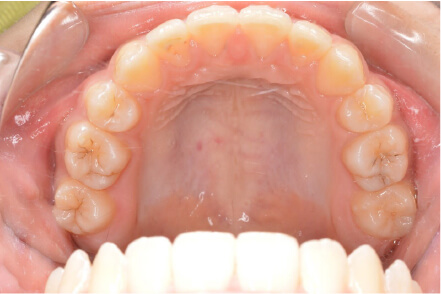

叢生の症例

11歳

女性

相談内容

上の前歯の歯並びが気になる(マイオスマイルからの移行)

カウンセリング・診断結果

インビザライン、拡大入れながらスペースを作成、下Eは出てきたら削りながら進める

治療内容・方法

全額アライナー矯正 クリアコレクト

術後の経過・現在の様子

クリアライナー使用

治療のリスク

痛み・歯根吸収・歯肉退縮・虫歯・後戻り

費用・治療期間

移行料金220,000円、月々16,500円、1年1ヶ月+myo2年3ヶ月